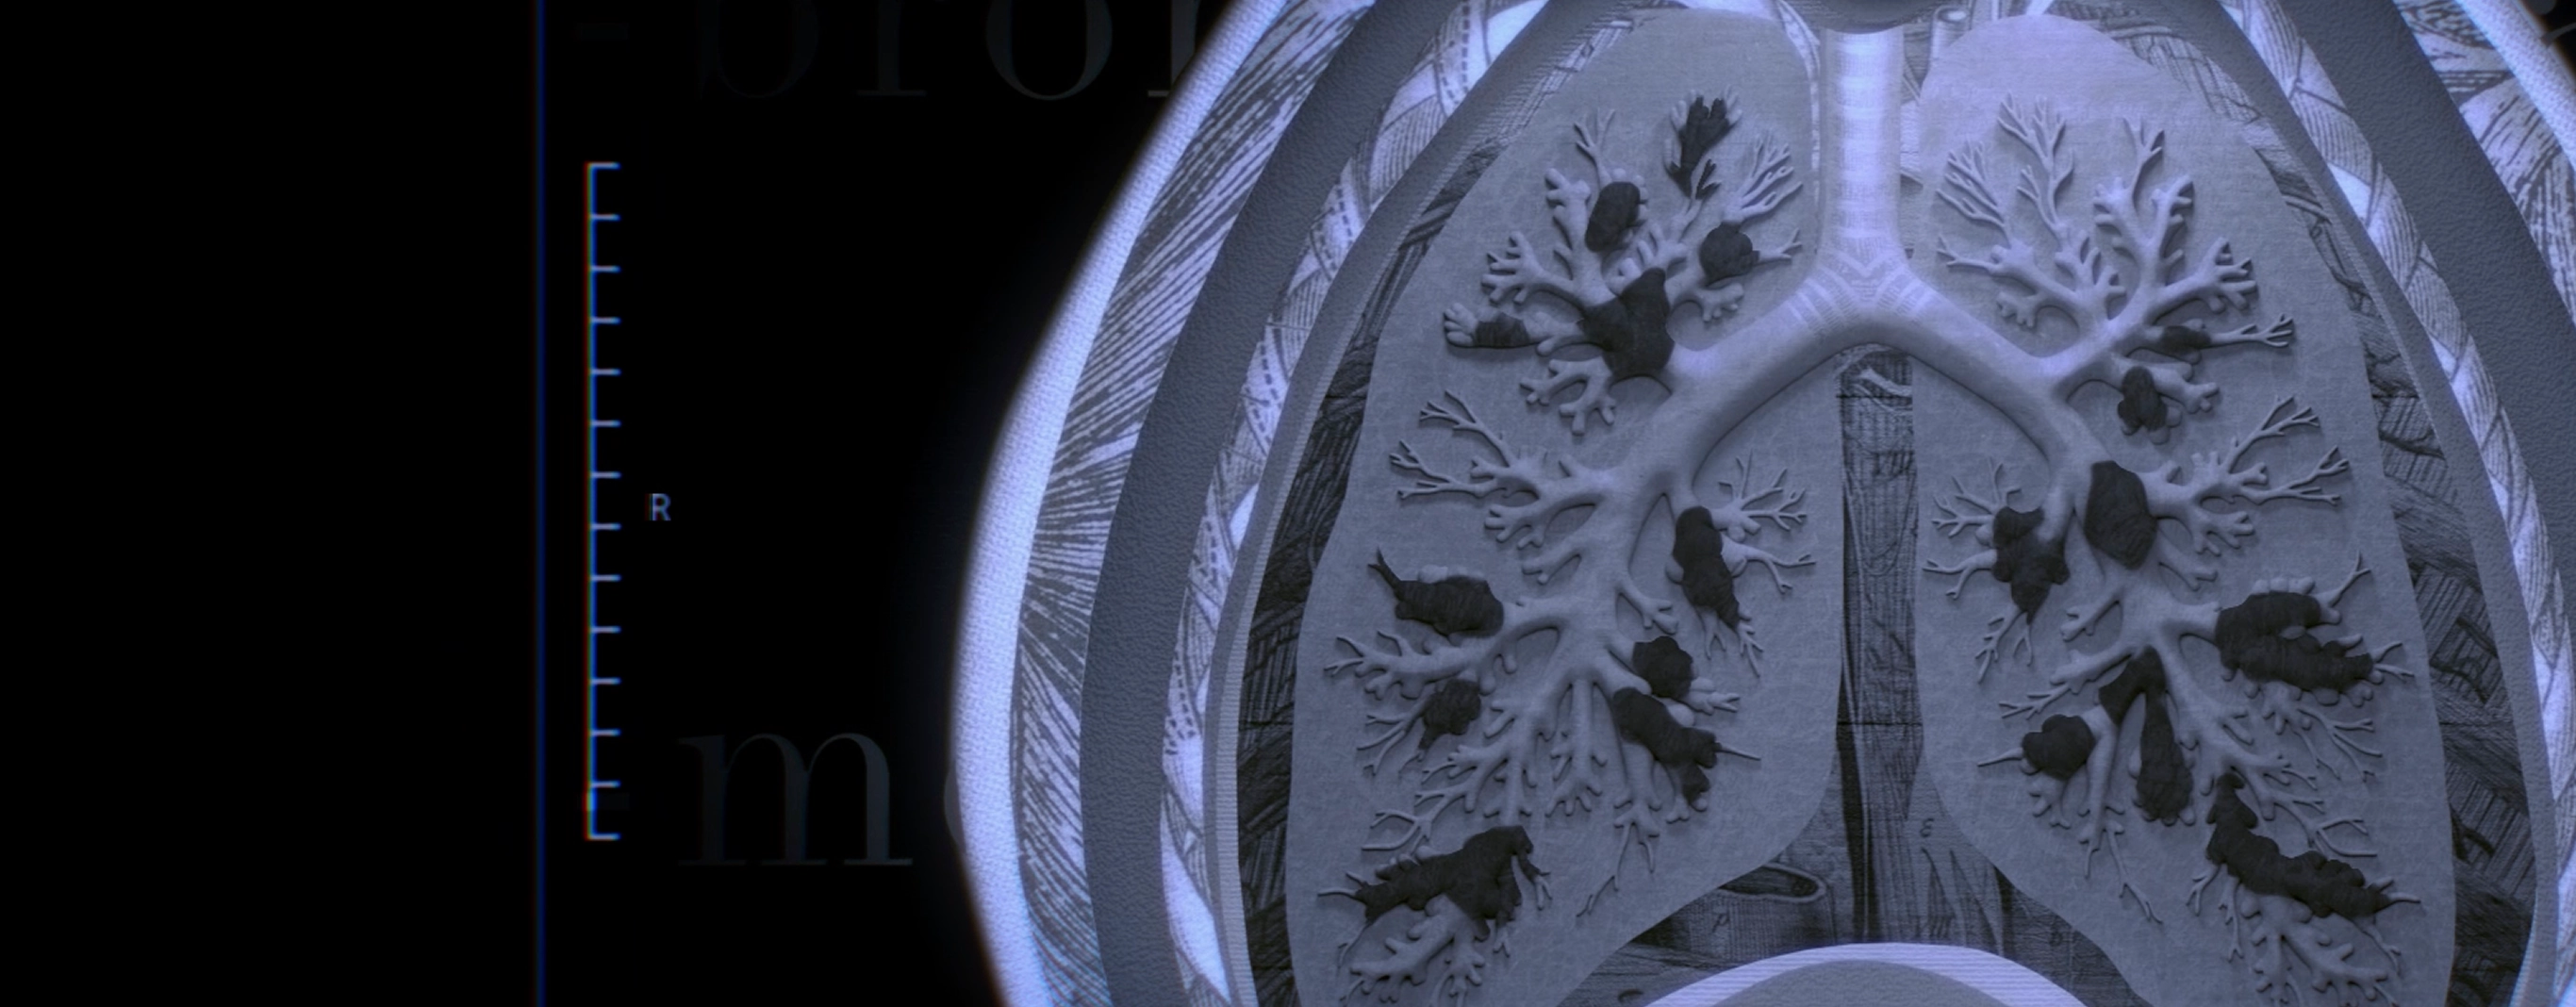

A CT scan is the standard way to determine if you have bronchiectasis.

A CT scan can rule out or confirm bronchiectasis.

A CT scan is a type of chest scan that provides clear, detailed images of the lungs. It’s used to diagnose BE because it can reveal widening of the bronchi—a sign of the disease that tests like an X-ray might miss.

A CT scan of a lung with bronchiectasis